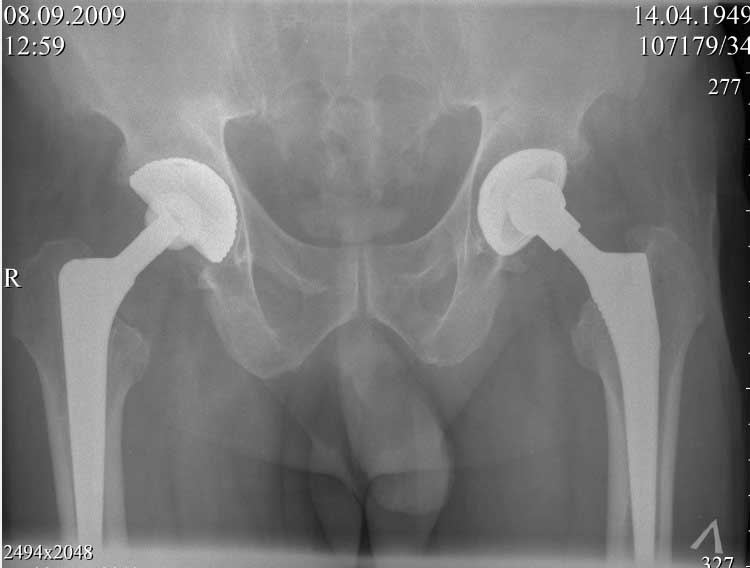

далее снимок в 2009 году

В конце 2008 года отметил боли в правой паховой области при опоре на правую ногу. На рентген снимках таза с тазобедренными суставами явных признаков нестабильности вертлужного компонента не обнаружено. В 2009 году нейрохирурги его "успешно" прооперировали на L\3-\4 связывая болевой синдром в правой паховой области с наличием грыжи указанного межпозвонкового диска. Состояние только ухудшилось, больной уже не мог долго сидеть, боль прогрессировала . Его в 2009 и 2010 годах смотрел ортопед, делались рентгенснимки, но почему то приходили к выводу что эндопротез справа стабилен. В марте 2011 года я впервые увидел его, через одну неделю после этого был прооперирован. На операции вертлужный компонент при упоре на него инструментом прокручивался во впадине и без труда был извлечен.